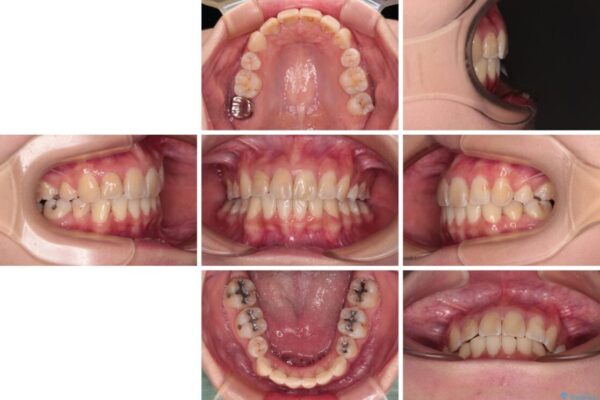

治療前

• デコボコと深い咬み合わせ ワイヤー装置での抜歯矯正 治療前画像